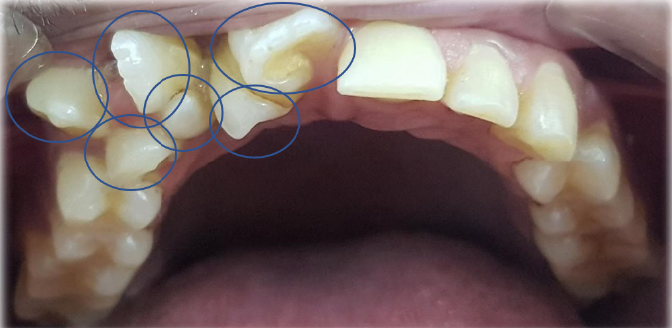

Case Report: A Strange Case of Self-Harm

Mariottini Gabriele and Castellani Roberto L. 5(10): 62-65.